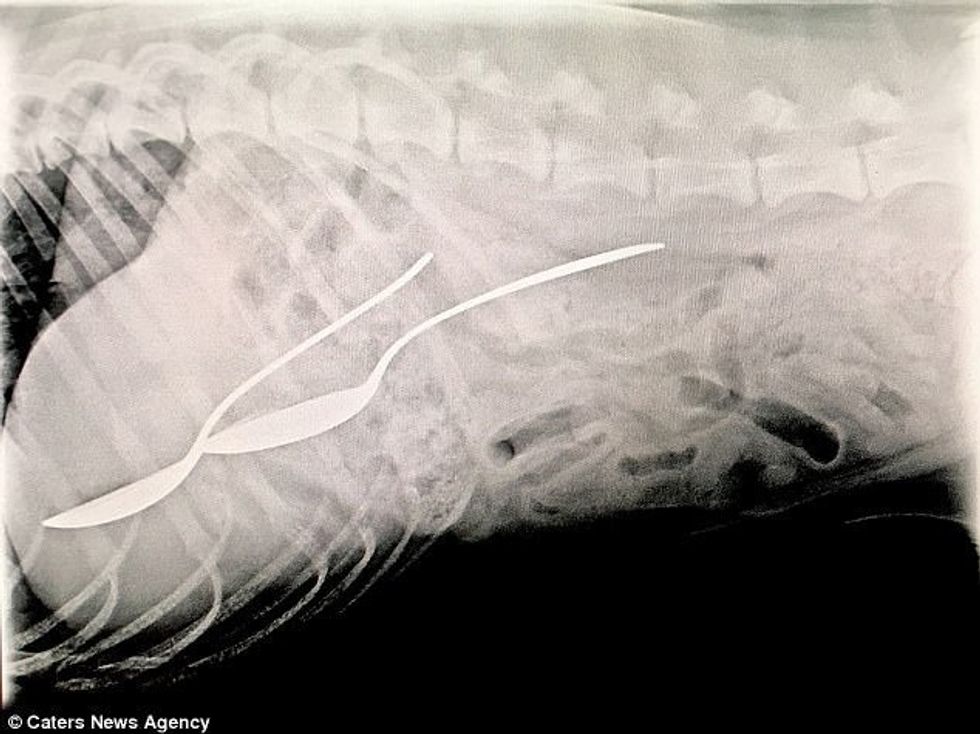

Skanimet kanë treguar për rastet më të pazakonta, prej lidhëseve të gomës, parave apo lugëve, që qentë i hëngrën duke menduar se janë ushqim. /Telegrafi/